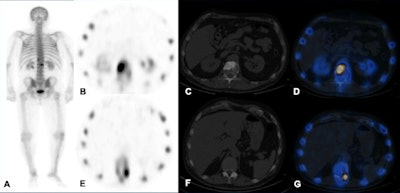

Technetium-99m MDP SPECT/CT examination. A: Whole-body image shows increased tracer uptake at T12 and L1 vertebrae in a patient with breast cancer. B-D: Increased tracer uptake in the sclerotic lesion in the L1 vertebra is in keeping with bone metastasis. E-G: Increased tracer uptake on the left side of T12 vertebra localizes to a facet joint (degenerative disease). All images courtesy of Dr. Oi Yean Wong and Dr. Gopinath Gnanasegaran."Skeletal metastasis is often a poor prognostic indicator and presents late when devastating complications such as fractures and spinal cord compression occur. Other significant complications include pain, hypercalcemia, and bone marrow suppression," they explained. "Therefore, it is important to detect skeletal involvement early and to determine whether patients respond to treatment."

Like planar scintigraphy, SPECT uses gamma rays. Both these modalities are highly sensitive, widely available, and relatively cheap. Compared with planar scintigraphy, which has poor spatial resolution (1 cm), SPECT-CT can more accurately localize metabolically active foci and characterize them, reducing equivocal reports and allows reliable identification of degenerative disease, often difficult to be distinguished from bone metastasis on other modalities, they stated.

Technetium-99m (Tc-99m) MDP is a bone-specific SPECT and planar scintigraphy tracer. Increased uptake occurs in areas of osteoblastic reparative activity. The main pitfalls are the following: